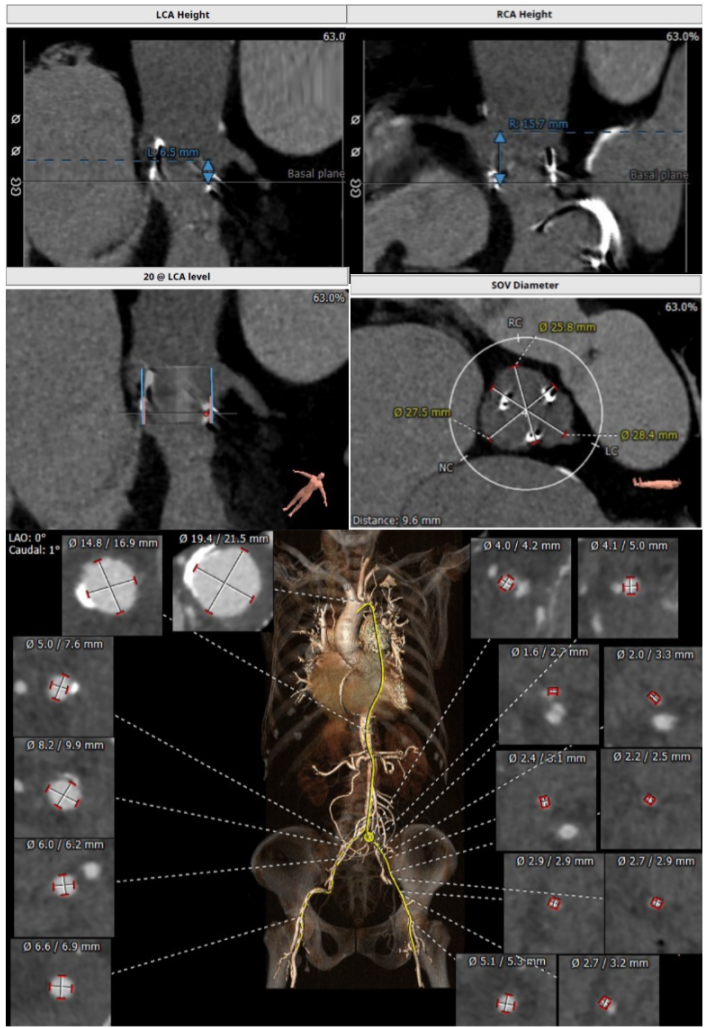

经过充分的术前食道超声及心脏CTA的评估,团队一致选择目前国际上瓣中瓣(Valve in Valve)技术使用最多最成熟的器械——Edwards SAPIEN3瓣膜。与林阿姨及其家属充分沟通后,在经验丰富的王焱院长的指导下,珠海市人民医院结构性心脏病团队决定为林阿姨同期进行主动脉瓣及二尖瓣的双瓣膜置换,采用的方案是先经股动脉途径为其行主动脉瓣的瓣中瓣植入(VinV TAVR),然后经股静脉途径,穿刺房间隔后,行二尖瓣的瓣中瓣植入(VinV TMVR),视情况对房间隔穿刺后的缺损进行封堵。

主瓣瓣中瓣CT评估

二尖瓣瓣中瓣CT评估